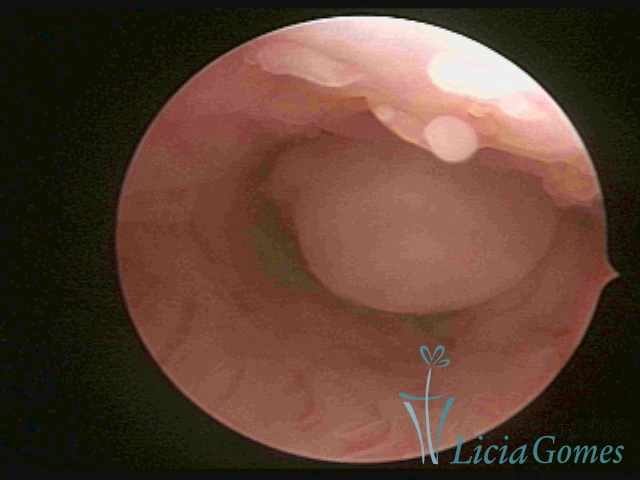

PÓLIPOS ENDOCERVICAIS

São tumores benignos, resultantes da proliferação focal reativa aos processos inflamatórios ou à situações de hiperestrogenismo, e podem ter sésseis (com a base de implantação larga) ou pediculados do epitélio.